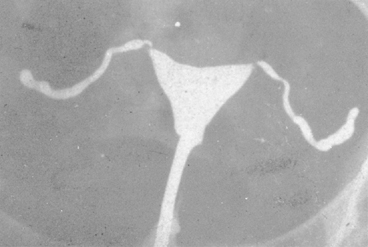

No characteristic radiographic features are pathognomonic for genital tract TB, although certain findings should raise suspicion of its possibility. Barter and associates reported that an abdominal film may show calcified pelvic and abdominal lymph nodes, a characteristic and recognized sequela of healed genital tract TBs.83 Hysterosalpingography may reveal certain abnormalities that suggest the possibility of pelvic TB. The uterine cavity is classically shriveled and deformed, with associated intrauterine adhesions and lymphatic extravasation (Fig. 6). The fallopian tubes often show ragged outlines with multiple strictures, giving a beaded appearance (Fig. 7); in some patients, the entire tube appears rigid and may exhibit small terminal sacculations of the ampullary end (Fig. 8). Fistulous tracts between the genital tract and other pelvic organs may be identified. Occlusion of the digital end of the fallopian tubes is common, although marked hydrosalpinx is usually uncommon (Fig. 9), Calcification of the organs may be visualized.84,85 If a water-soluble contrast medium is used and the usual precautions are observed, complications can be minimized. Hysterosalpingography is contraindicated in the presence of recent acute pelvic infection, and many reports described exacerbation of pelvic TB following the procedure.86

Fig. 9. Gross dilatation and occlusion of both fallopian tubes is visible on this radiograph.